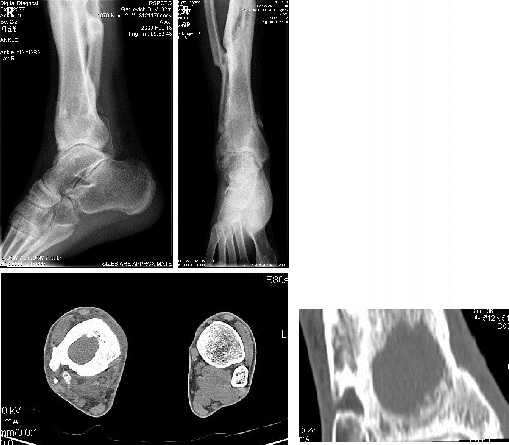

У пациента 31 года после ВКДО голени по Илизарову хронический остеомиелит дистального отела большеберцовой кости.

Пацент лечится у нас с 2005 года когда по поводу несращения с/3 голени был применен ВКДО по Илизарову. Достигнута консолидация, аппарат демонтирован. Через 2 года после сниятия аппарата появился свищ над внутренней лодыжкой. Осенью 2007 года - ФНЭ, аутопластика дефекта метафиза аутоспонгиозой из проксимального отдела большеберцовой кости - в течение года ремиссия.

В ноябре-декабре 2008 вновь открылся свищ, произведена хирургическая обработка, в настоящее время скудное серозное отделяемое. Конечность полностью опорна, болей нет.

Вопрос: чем лучше заполнить дефект метафиза: губкой из крыла подвздошной кости или каким-либо заменителем (хотя инфицирование остается)?